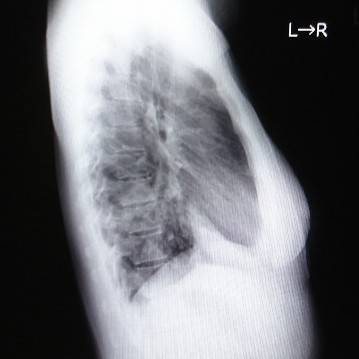

肺を横から撮影した写真がコチラです。

レントゲンでは見慣れないとなかなか見つけづらいですよね。